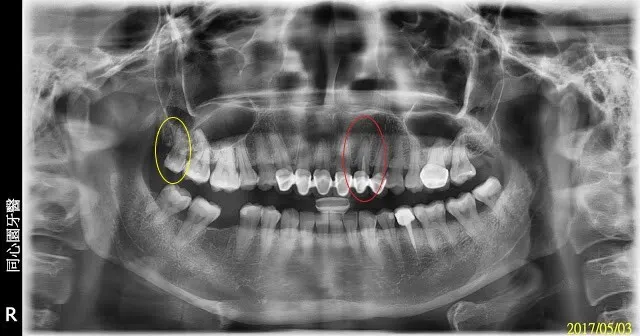

初診的病人,我都會照環口X光片檢查,像掃描,一次就可看到多數問題,所以我初診會講解很久很多,不會只針對主訴(主要的問題),請把握

環口x光片檢查,也看不出所以然(蛀牙)。如果X光片很明顯就看得出是蛀牙、牙齒裂掉頂多知道,很明確就看得出造成牙痛的兇手是誰,那不見得是件好事,有點像『可以被檢查出的大多已是癌末』的概念...別擔心,這裡我只是比喻嚴重性,牙科的問題很少會變成癌症的。

左上側門牙(紅圈)有抽過神經(根管治療)過(白白的一條,是根管充填的材料,x光只有黑白兩色,實際是偏橘紅色的,請繼續往下看),而且這根管治療的品質並不太理想(什麼叫較為理想的根管治療品質?剛好她左下就有個對照組),且有根尖陰影(病變)。

右上最後的第三大臼齒(智齒,黃圈),疑似有蛀牙。

有疑慮時,我會建議病人再照張不同角度或種類的X光片確認。

我這裡要說的是,牙套,不管哪種材質,都有很好的X光遮蔽性,會造成判讀上的困擾,把真正的問題遮蔽住(說難聽點就是粉飾太平)。X光只是輔助,再加上臨床上檢查,才能較逼近真正的診斷…西方這叫鑑別診斷Differential Diagnosis(D/D),東方中醫叫望聞問切,線索越多越好,〔我們醫護人員臨床的工作其實跟抽絲剝繭的偵探很像〕。